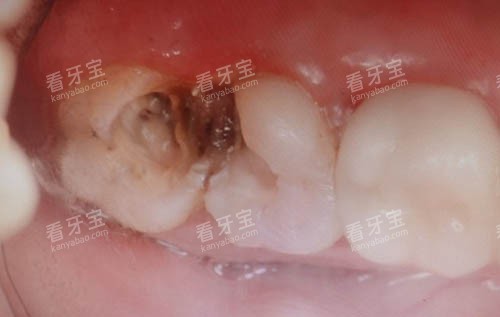

树脂补牙:针对浅中度龋齿,国产树脂材料价格约为 120 元起至 200 元左右每颗;进口纳米树脂因耐磨性和美观度更佳,价格在 260 元起至 450 元左右每颗。

嵌体修复:对于缺损较大的牙齿,嵌体是比传统补牙更优的选择。

铸瓷嵌体价格通常在 1200 元起至 1800 元左右,全瓷嵌体则在 1600 元起至 2500 元左右。

根管治疗:根据牙齿牙根数量不同收费各异。

前牙单根管治疗价格约为 300 元起至 500 元左右;前磨牙双根管在 500 元起至 800 元左右;后磨牙多根管治疗复杂,价格在 800 元起至 1500 元左右。

若需显微根管治疗,费用会额外增加 500 元至 1000 元。